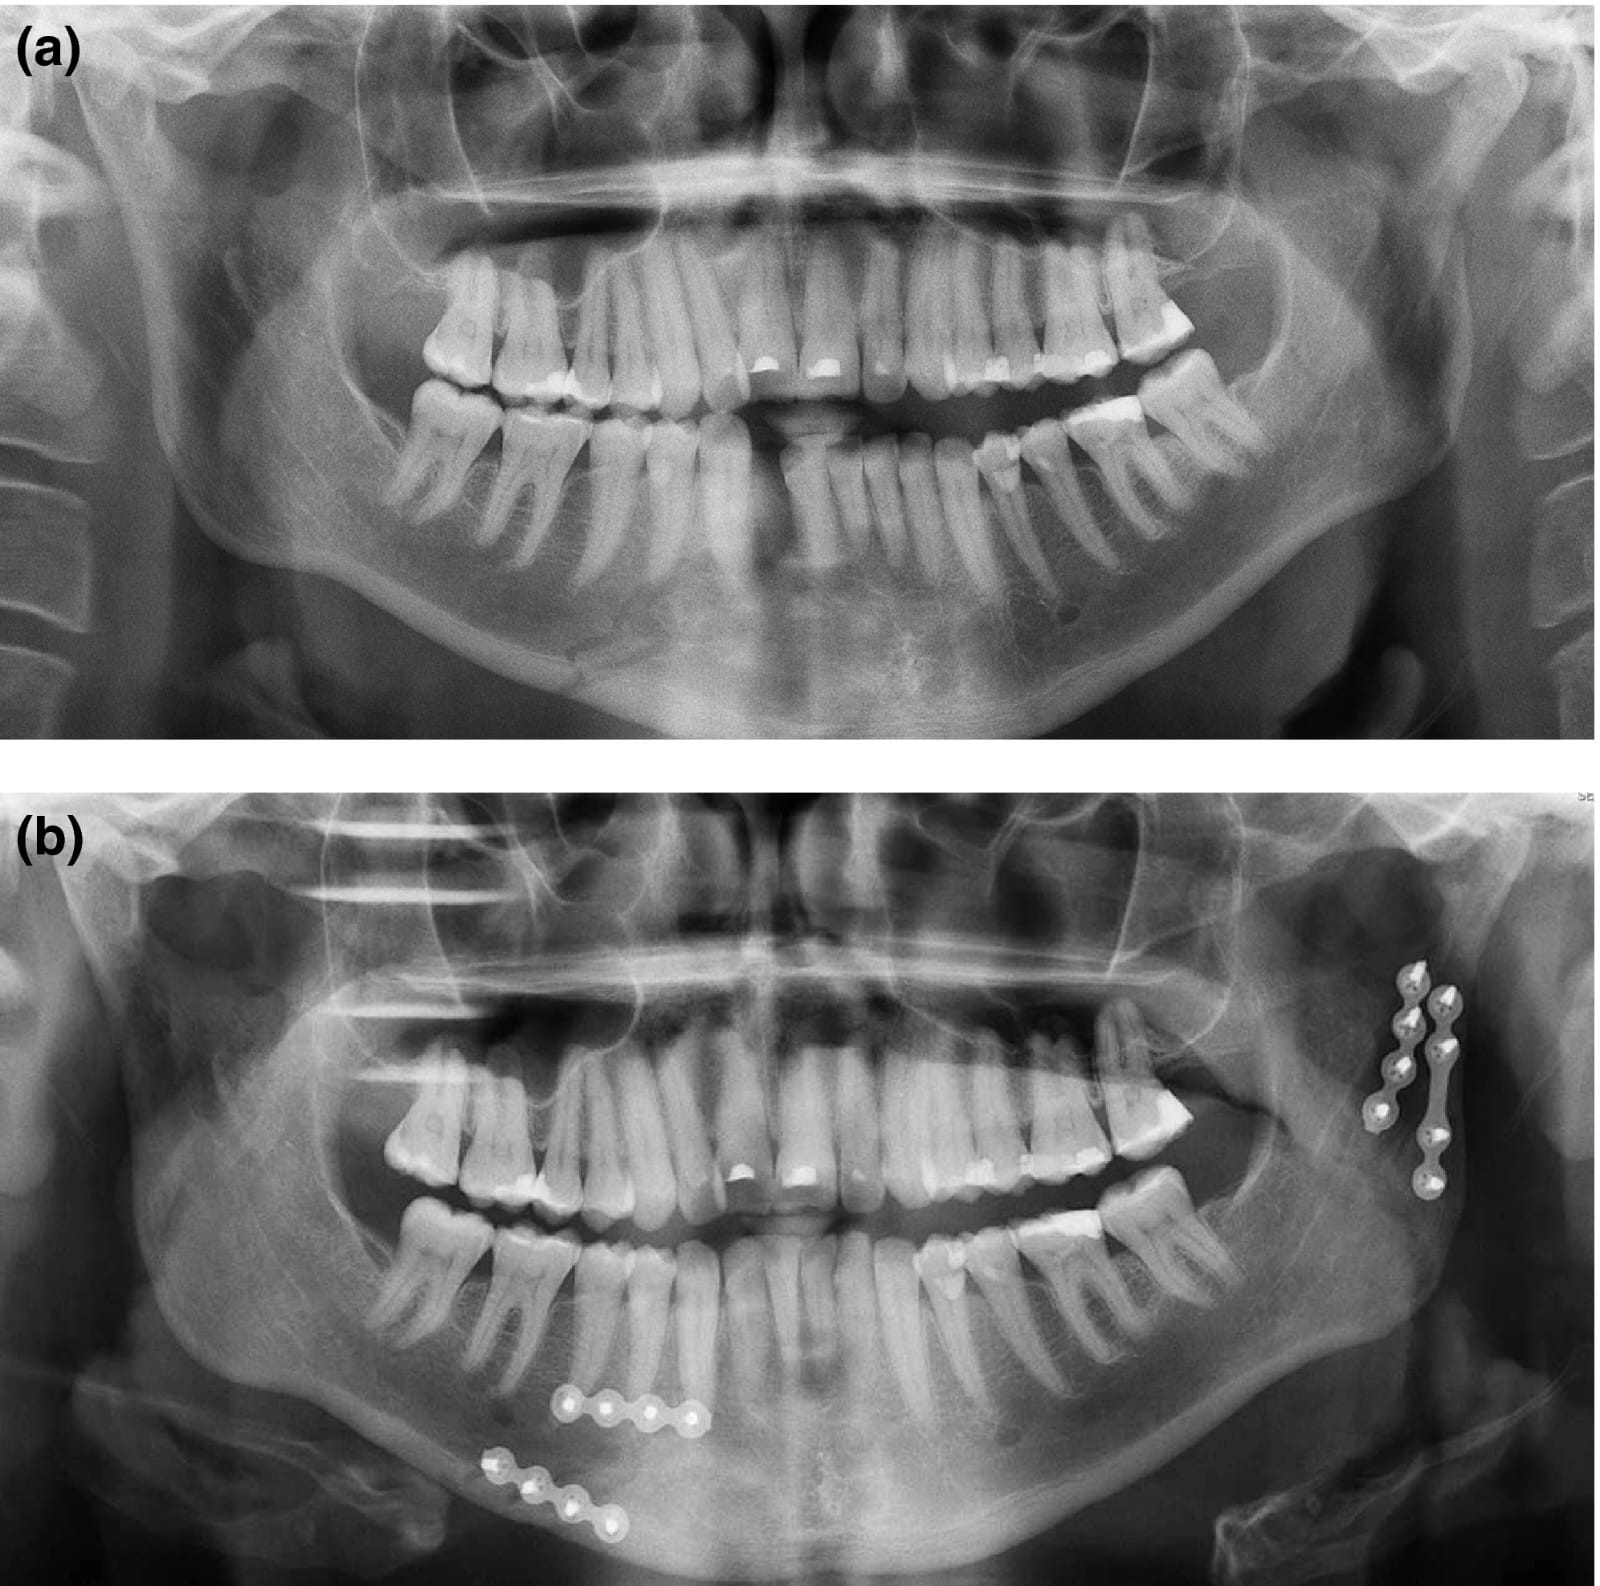

Appropriate diagnosis and a timely response will improve outcomes when managing traumatic dental injuries. Teeth can be broken during sports, games indoor or outdoor activity or fall in children and adults. Tooth may even come out of the socket (avulsion) or get deep into the socket (intrusion) during a fall or hit.

In many cases of traumatic dental injuries, the timeliness of care is key to saving the tooth. It is thus important for all dentists to have an understanding of how to diagnose and treat the most common dental injuries.